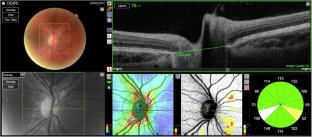

Peripapillary hyperreflective ovoid mass-like structures (PHOMS) have been recently described on optical coherence tomography (OCT) scans of the optic nerve. We aim to determine if there is a causal relationship between OCT measurements of the optic disc area (DA), scleral canal diameter (SCD) and refractive error (spherical equivalent, SE) on the presence of PHOMS.

Retrospective analysis of OCT scans which were graded for the presence or absence of PHOMS in children with suspected papilledema was undertaken. Data on disc area, DA (mm2) and scleral canal diameter, SCD (µm) were obtained from OCT scans. Statistical analysis was performed on two subgroups: unilateral PHOMS vs contralateral control; all eyes with PHOMS vs all eyes without PHOMS (controls). Logistic regression analysis was performed.

In unilateral PHOMS (n = 32), there was a non-significant tendency towards a larger DA and SCD in the eye with PHOMS (3.33mm2, 1701 µm) compared to the contralateral eye in the same patient (2.83mm2, 1556 µm). Wider analysis of all eyes with PHOMS (n = 116) versus all eyes without (n = 104) showed there was a significant difference between the DA (3.38mm2 versus 2.65mm2 p = <.0001) and SCD (1763 µm versus 1571 µm, p = <.0001). Logistic regression showed that SCD made a significant contribution to predicting the presence of PHOMS (OR 1.0042, p = 0.0017).

PHOMS are frequently seen in pseudopapilledema. It would be useful to understand their pathophysiology as an accurate diagnosis in the context of the asymptomatic paediatric population is crucial. We report that a wider scleral canal diameter was significantly associated with the presence of PHOMS.